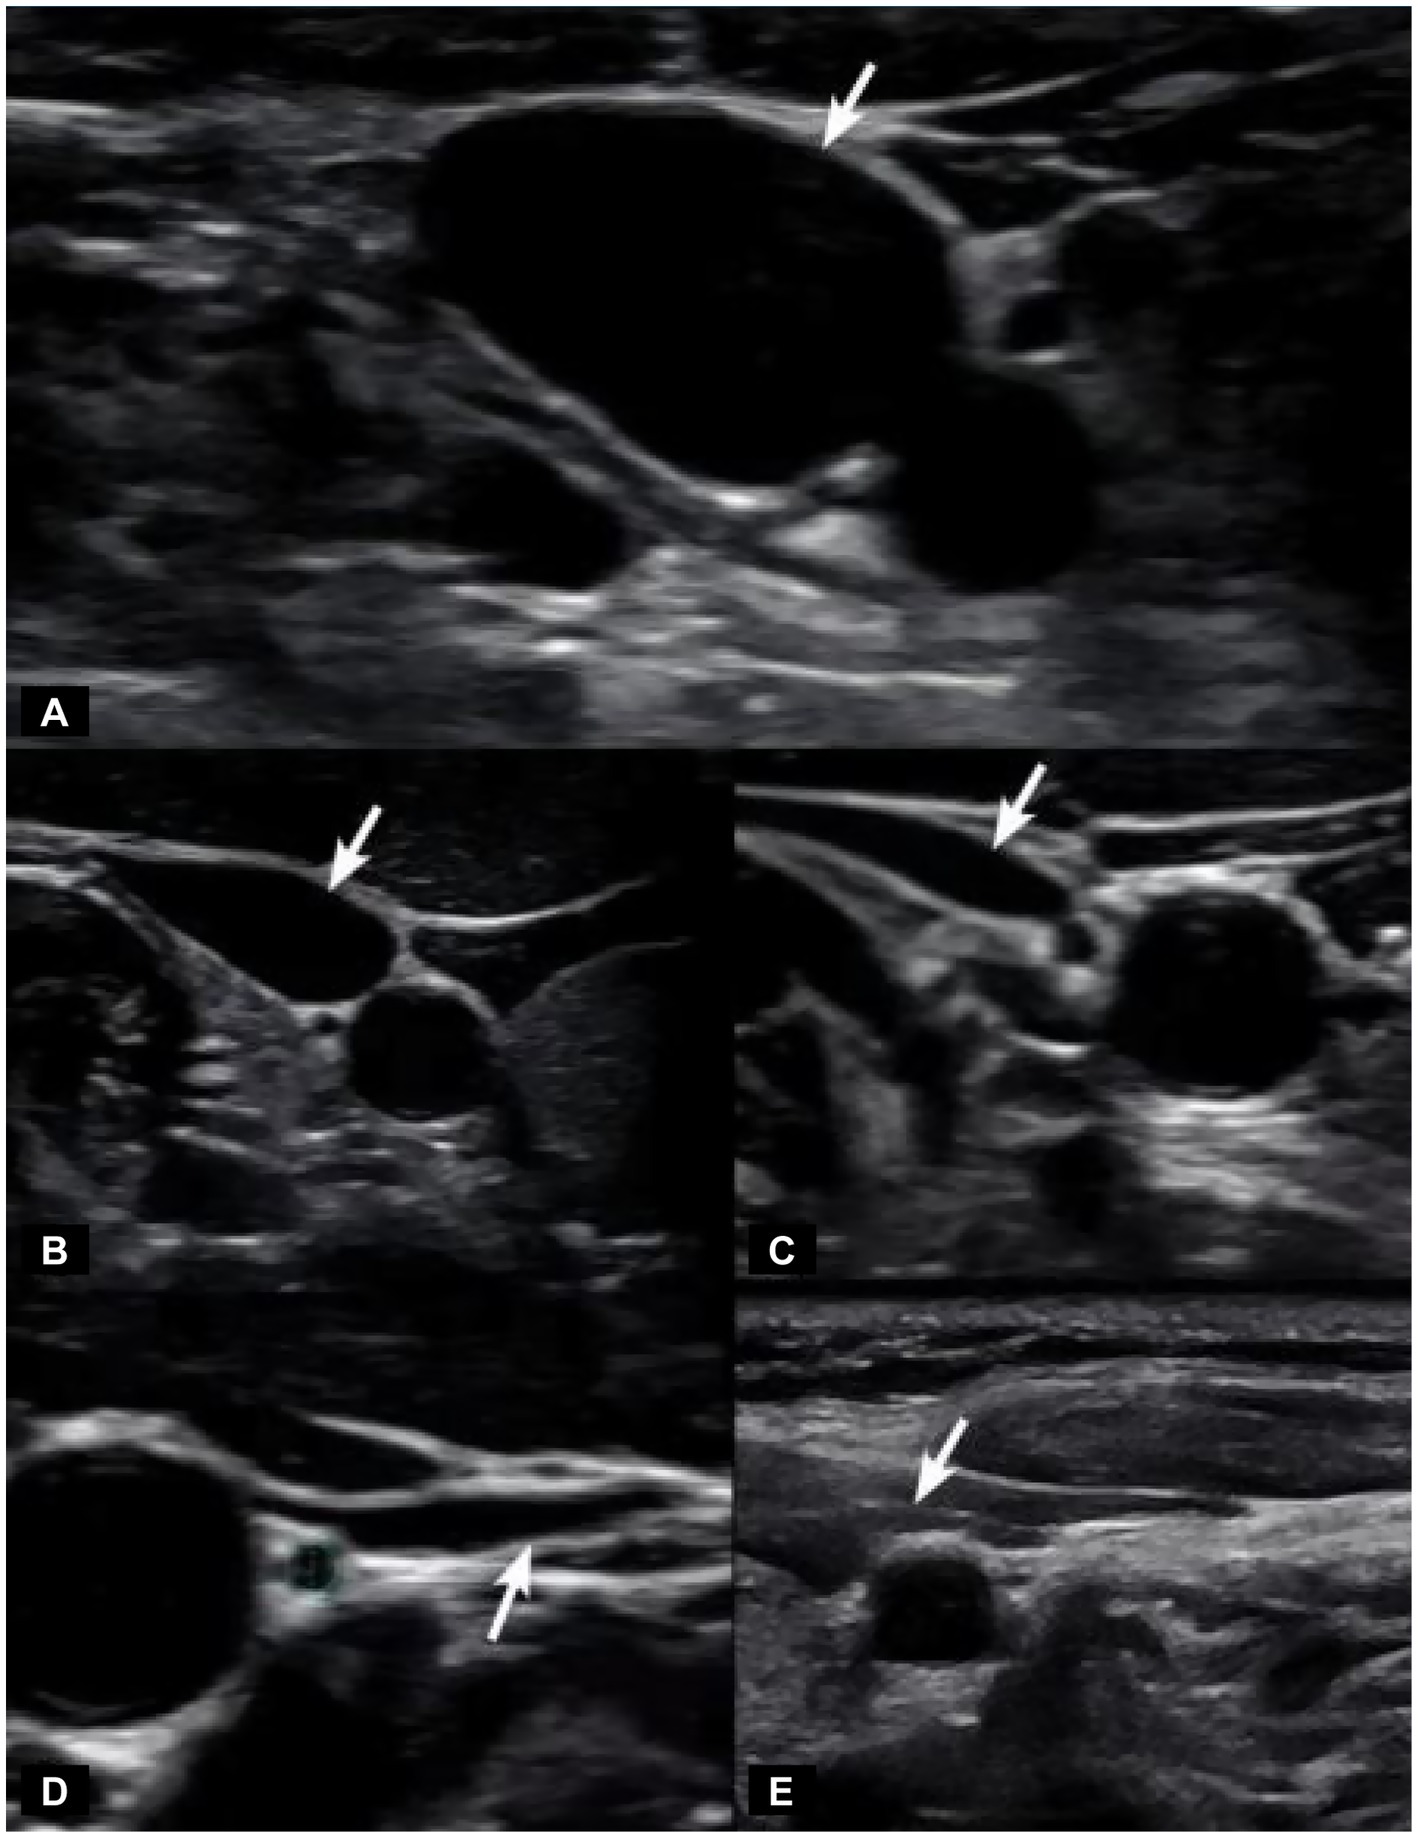

IJV CSA is easily measured under B-mode ultrasound (see Figure 8). Unilateral normal IJV CSA in the supine position is >90–100 mm2 (44–46). As IJV CSA is typically measured in the mid-cervical region, our study documents that measuring it at the level of the atlas was a more sensitive test for IJV compression when evaluating with ultrasound (42, 47). Not only does LCI promote excessive motion of the atlas, but as the cervical curve breaks down, the atlas shifts forward in 3-D space. In our patient population, the documented LCI, decreased DOC, and increased C6AI likely account for the bilateral IJV compression at C1.

Figure 8. Degrees of internal jugular vein compression as seen on ultrasound examination of the neck. (A) Normal “open” internal jugular vein. (B) Slightly compressed. (C) Moderately compressed. (D) Severely compressed. (E) Completely closed. It is internal jugular vein compression (arrows), especially with upright posture and neck motions, that leads to intracranial hypertension (increased brain pressure).